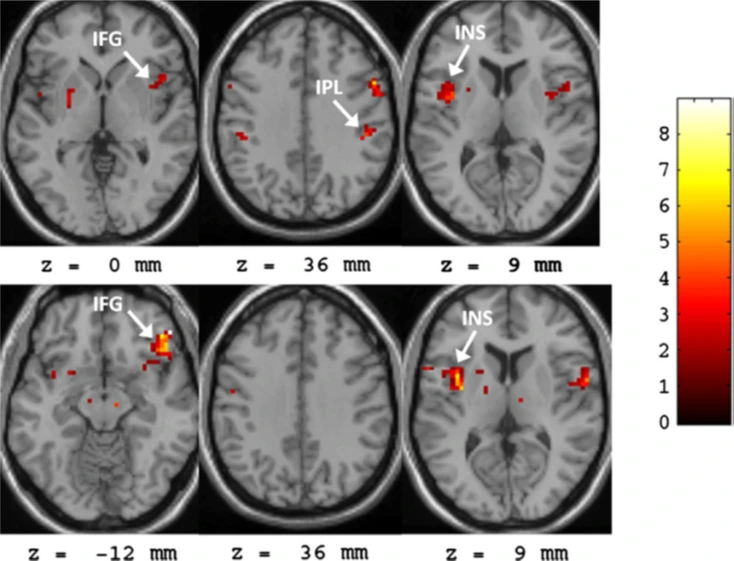

인간의 저작활동 역시 효율적인 소화기능을 위해서 뇌의 편측화가 진행된 움직임입니다. 인간의 씹기 동작에 대한 다음 뇌의 활성화 논문을 보면 이해가 됩니다.

한쪽으로 껌을 씹는 동안 뇌의 활성화되는 구역을 기능적 뇌자기공명영상 (fMRI)를 통해서 확인한 연구입니다. (참 별 걸 다 연구하죠^^;;;)

씹기를 담당하는 운동과 감각 구역은 오른쪽으로 씹는 경우 왼쪽 대뇌반구가. 왼쪽으로 씹는 경우 오른쪽 대뇌반구가 담당해서 활성화됨을 알 수 있습니다. 즉 씹는 동안 우리의 뇌는 한쪽만 활성화가 진행되지 동시에 활성화가 혹은 동일하게 활성화가 되지 않는다는 것입니다. 씹기는 양쪽 턱이 동시에 움직인다고 생각했지만 뇌의 조절은 그렇지 않다는 것입니다.

조금 어려운 구역이지만 이 구역들은 중추패턴발생기(CPG)라는 구역들입니다. 이 구역은 걷기와 같이 리듬이 있는 동작을 수행할 때 앞서 보여드렸던 대뇌반구가 계속 의식해서 움직임을 조절하지 않고 무의식적, 자동적으로 움직임을 율동적으로 만들어 낼 때 활성화 되는 구역들입니다. 즉 씹기라는 동작은 의식해서 움직임을 제어하기도 하지만 무의식적, 자동적으로 움직임이 제어되기도 한다는 것입니다.

이 사진은 저 스스로도 논란의 소지가 있다고 생각하지만 활성화가 나타난 저 구역들은 인간의 감각, 운동, 기억등 다양한 정보들이 모두 모이는 곳입니다. 보통 신경과학자들은 저 구역이 인간의 창의력과 관련 있다고 생각한답니다. 즉 이 연구 결과만 놓고 본다면 씹기를 하는 동안 인간의 뇌는 창의력에…. 더 이상 확대 해석은 하지 않겠습니다^^ (하지만 재밌는 결과인 것은 분명합니다.)